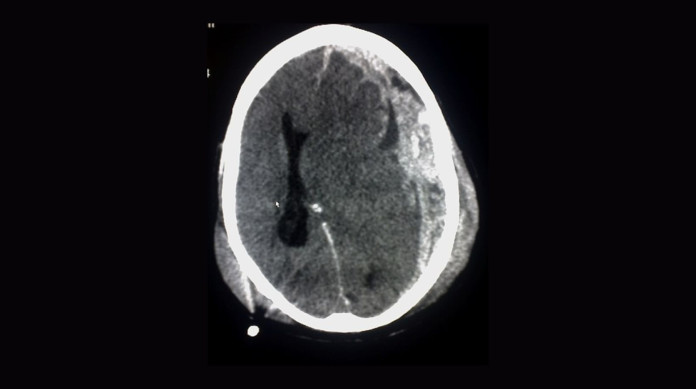

Um hematoma subdural, também conhecido como hemorragia subdural, é caracterizado como uma emergência médica, quando o sangue fica acumulado entre o cérebro e o crânio.

Magalhães destaca a divisão da condição em hematomas subdurais agudos e crônicos. Os agudos estão diretamente relacionados ao trauma e aparecem nas primeiras 24 a 72 horas, com caráter usualmente mais crítico, incluindo risco de sangramento intracraniano.

Para o hematoma subdural agudo, os sintomas existentes incluem dor de cabeça, algum hematoma subgaleal — o conhecido “galo” na cabeça — e alterações neurológicas associadas, como sonolência e confusão mental. Estes podem evoluir ainda para estupor e coma, além do risco agregado de morte.

“Essa cefaleia, essa dor de cabeça, pode se associar a vômitos e outras alterações neurológicas focais, como fraqueza no corpo, alteração de sensibilidade de um lado e alterações pupilares, ou seja, a dilatação de uma das pupilas”, esclarece Samir Magalhães.

O tratamento apresenta uma opção cirúrgica, quando o hematoma subdural agudo pode ser drenado, dependendo de seu volume e impacto na estrutura do cérebro.